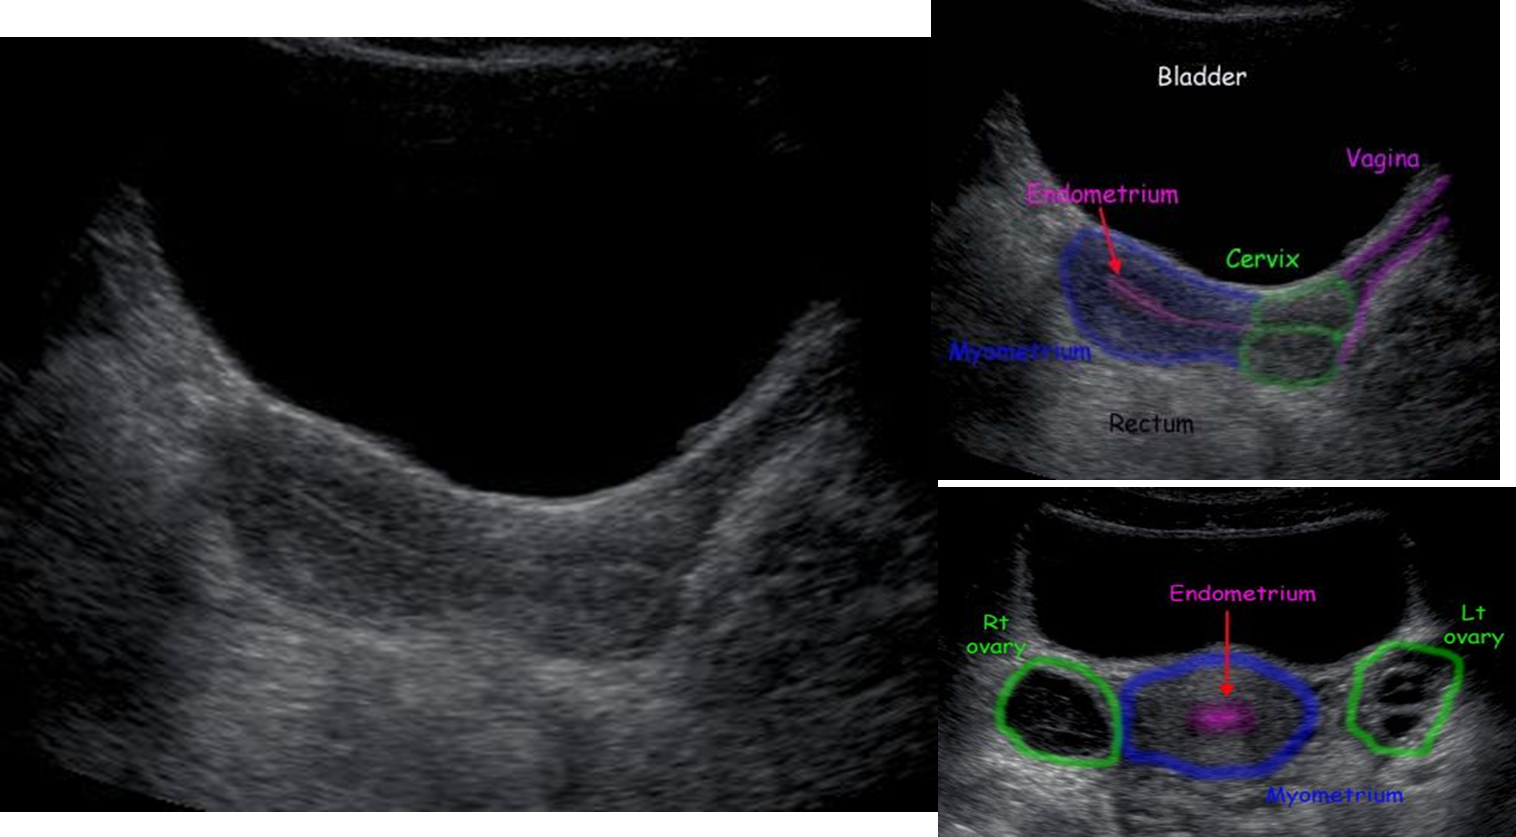

Trans abdominal ultrasound(Need full bladder) vs Trans vaginal ultrasound (Need empty bladder)

Normal uterus on trans-abdominal ultrasound Longitudinal and transverse views

- The myometrium shows low level echoes, whereas the endometrial cavity gives a an echogenic linear stripe